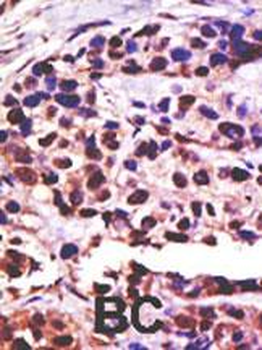

Formalin-fixed and paraffin-embedded human cancer tissue reacted with the primary antibody, which was peroxidase-conjugated to the secondary antibody, followed by DAB staining. This data demonstrates the use of this antibody for immunohistochemistry; clinical relevance has not been evaluated. BC = breast carcinoma; HC = hepatocarcinoma.